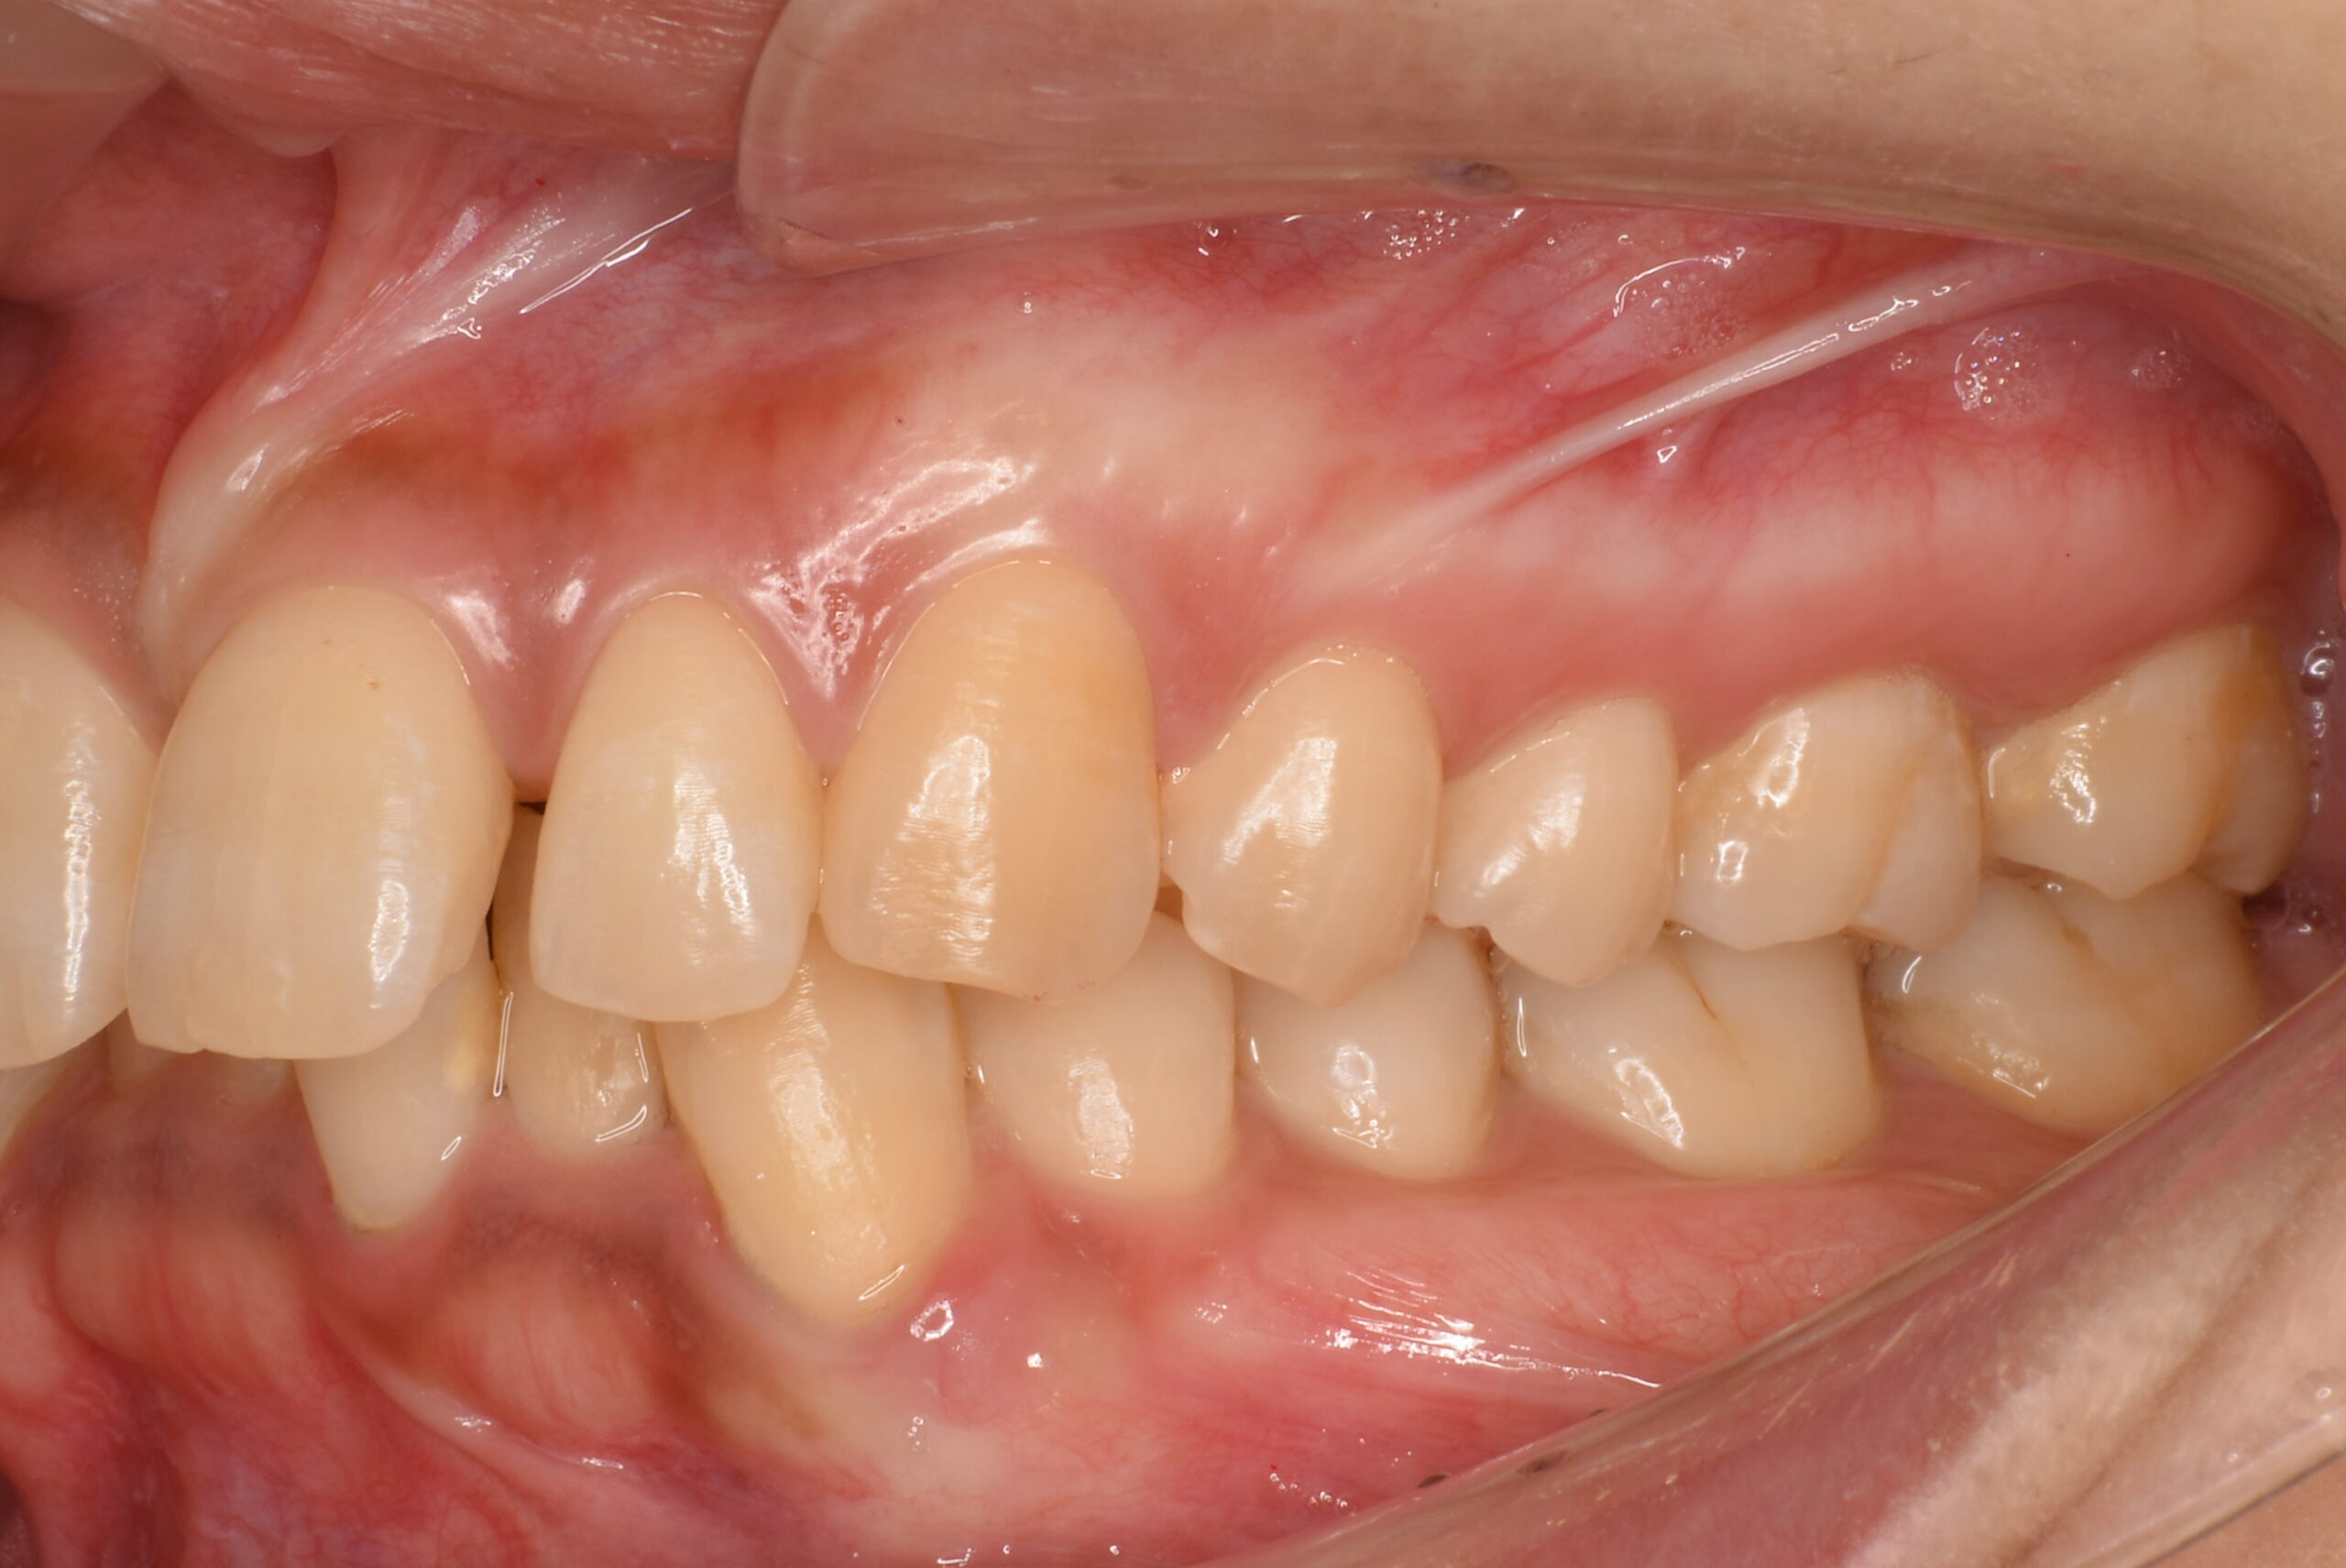

- BEFORE

治療前_左側方

| 治療内容 | 患者様は、上下顎前歯部の叢生(歯のガタつき)や歯間空隙(すきっ歯)、前歯の唇側傾斜(前突/出っ歯)を主訴に来院されました。 診査の結果、抜歯を行わずに歯列全体の配列改善が可能と判断し、マウスピース型矯正装置(インビザライン)による非抜歯矯正を計画しました。 初診時には歯周病の初期症状である、歯肉の炎症および出血傾向が認められたため、矯正治療と並行して歯周治療(プラークコントロール・スケーリング)を実施し、口腔衛生環境の改善にも取り組みました。 |